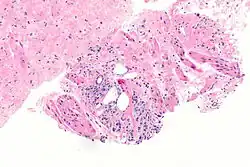

Przerzuty gruczolakoraka do płuc

Podopłucnowe przerzuty raka gruczołu krokowego szerzące się drogą naczyń limfatycznych (lymphangitic carcinomatosis)

Znacznemu zaawansowaniu miejscowemu zwykle towarzyszą przerzuty odległe[185]. Rak gruczołu krokowego najczęściej daje przerzuty do węzłów chłonnych, kości i płuc[186]. Szerzenie się drogą naczyń chłonnych skutkuje zajęciem węzłów chłonnych[186]. Zajęcie poszczególnych grup węzłów chłonnych odbywa się zgodnie z drenażem limfatycznym narządu[187]. Przerzuty w węzłach chłonnych najpierw stwierdza się w grupach węzłów poniżej rozwidlenia tętnicy biodrowej wspólnej: w węzłach biodrowych wewnętrznych i biodrowych zewnętrznych, następnie dochodzi do zajęcia węzłów biodrowych wspólnych, okołoaortalnych i pachwinowych[186]. Rozsiew drogą krwionośną skutkuje powstaniem przerzutów odległych, które najczęściej pojawiają się w szkielecie osiowym, a rzadziej w płucach, wątrobie i innych narządach[147]. Przerzuty w kościach zwykle mają charakter osteoblastyczny (80%), ale możliwe są zmiany osteoblastyczno-osteolityczne (15%) i osteolityczne (5%)[187][185]. Przerzuty kostne często lokalizują się w kręgosłupie, szczególnie w odcinku lędźwiowym i piersiowym, nasadach kości udowych, miednicy, żebrach, mostku i czaszce[185][186][154][187]. Przerzuty do płuc, wątroby i innych narządów występują raczej w późnym przebiegu choroby i dotyczą one odpowiednio 25% i 20% chorych[186][187].